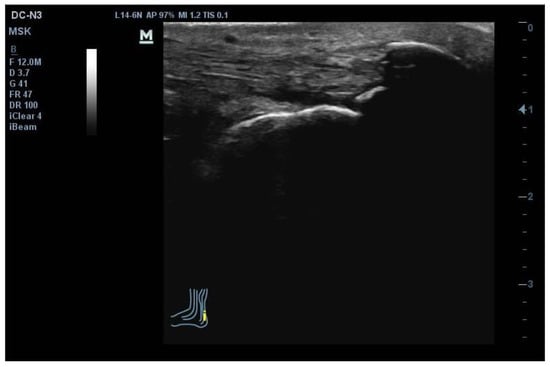

2.4. Ultrasound Imaging Assessment